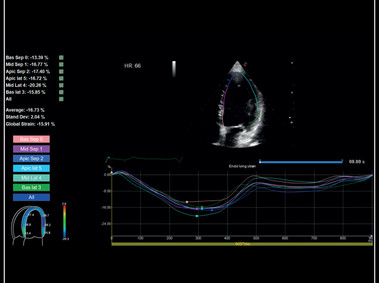

Đánh giá vận động vùng tâm thất trái toàn diện với Siêu âm đánh dấu mô cơ tim X-strain